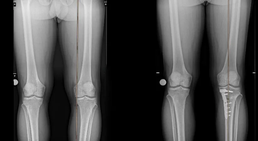

Beinachsenkorrektur bei X- und O-Bein Fehlstellungen

Die Ursachen für eine Beinachsfehlstellung können vielfältig sein. Neben angeborenen Fehlstellungen unterscheidet man auch im Laufe der Lebensjahre erworbene...